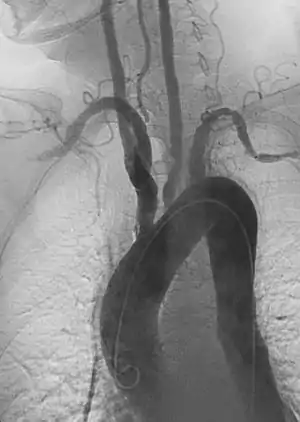

- Aortic aneurysms include thoracic, abdominal or thoracoabdominal. Treatment strategies are customized depending on the location, size, rate of growth and extent of the aneurysm as well as the medical comorbidities of the patient. For example, an intact, small but slowly growing aneurysm may be safely monitored with serial imaging for months or years before elective repair is considered. Elective endovascular aortic grafting is now routinely attempted when possible. Endovascular aortic repair (EVAR) refers to treatment of an abdominal aortic aneurysm, while thoracic endovascular aortic repair (TEVAR) is performed on the thoracic aorta. A ruptured aneurysm may be taken emergently for open, endovascular or combination repair.

A variety of endovascular grafts are available, and each has advantages and disadvantages depending on the characteristics of the aneurysm and patient.[89]